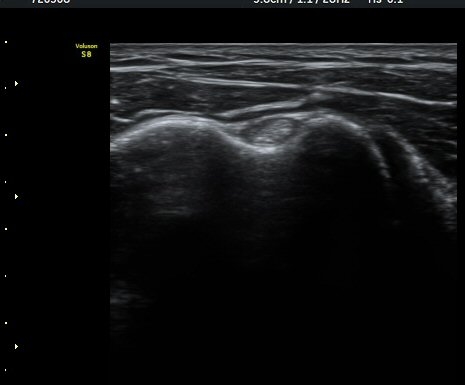

¾î±ú ¾Õ À̵ιڱ٠Ⱦ´Ü¸é°Ë»ç¿¡¼­ ÀÌºÎ¹Ú±Ù°Ç °í¶û ¾Æ·¡ ºÎÀ§¿¡¼­ À̵ιڱ٠ÀåµÎ ÁÖÀ§¿¡

¼ö¾×Àú·ù°¡ °üÂûµÈ´Ù(±×¸² 1, 2). °ß°©ÇÏ±Ù°Ç Á¾´Ü¸é°Ë»ç¿¡¼­ °ß°©ÇϱٰÇÀÇ °üÀý³»ºÎÀ§(±×¸² 3)